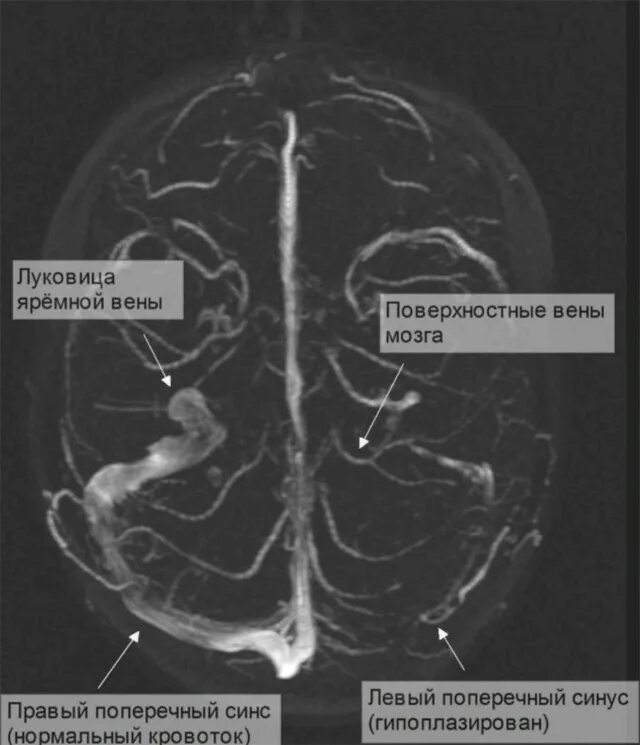

Синусы мозга мрт